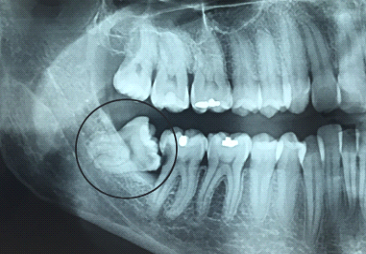

Na imagem abaixo vemos um siso impactado,

gerando cárie no Segundo Molar a sua frente, com evidente indicação de extração: